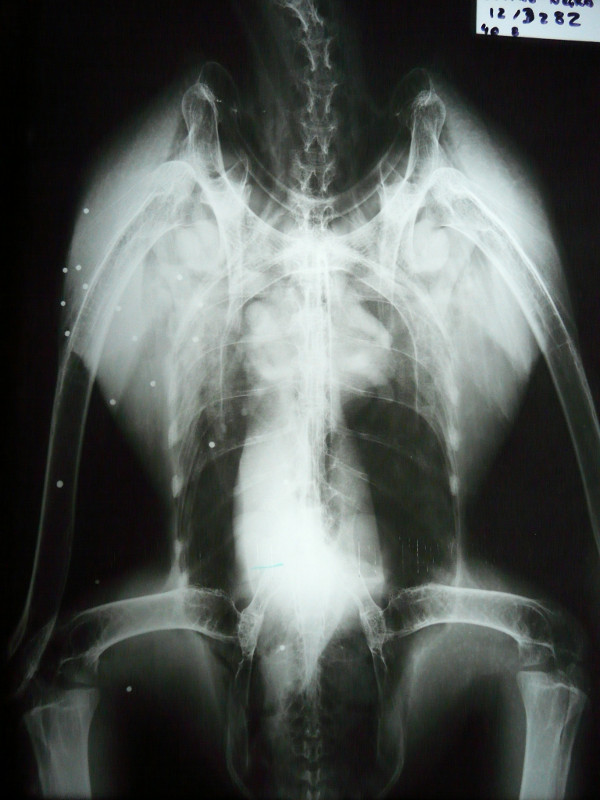

Por otro lado, y con mucha peor suerte, el domingo 11 de Noviembre ingresaba el ejemplar de buitre negro con signos de traumatismo, débil y deprimido, apenas se ponía en pie y tenía un ala descolgada. Se diagnosticó una fractura de radio y luxación de codo, pero su estado era tan grave que se decidió esperar 24 horas para realizar la radiografía, en la que encontramos más de 25 perdigones distribuidos por todo el lateral derecho del cuerpo y algunos dentro de la cavidad corporal y en la cabeza, confirmando además nuestros peores temores: había fractura también de húmero a nivel del codo, lo que hacía que este ejemplar de buitre negro ya apuntara como irrecuperable para el resto de sus días. El desplazamiento de los fragmentos en la zona de la articulación del codo había provocado una inflamación gravísima en la zona y destrucción de los tejidos blandos (musculatura, cápsula articular, ligamentos) y empezaba a haber pérdida de sensibilidad y fallo vascular en la parte más distal del ala.

Decidimos intervenir quirúrgicamente el pasado miércoles viendo que la inflamación del codo iba cada vez a peor y que el animal estaba dejando de comer por el dolor y las molestias. Durante la cirugía pudimos comprobar que la vena cubital había sido dañada por los fragmentos de hueso y se había producido una acumulación severa de líquido, además de inicio de necrosis de algunos músculos y tendones.

La tremenda decisión que tuvimos que tomar fue la de amputar el ala a nivel del húmero distal (para conservar la mayor longitud de ala posible). Tras 4 largas horas de cirugía, el animal despertó y hoy está comiendo bien de nuevo aunque aún adaptándose a la pérdida de un ala casi completa. Su futuro será pasar a formar parte del núcleo reproductor de GREFA, sabiendo que nunca más podrá volver a volar y pasar el resto de su vida en las mejores condiciones posibles pero en cautividad.